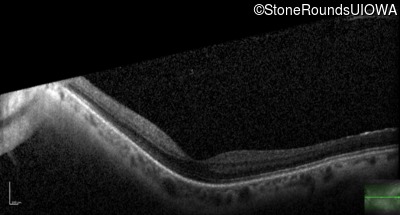

Age at visit: 41 years (Visit 2)

OD OS

This 41 year old woman was highly myopic as a child and experienced a rhegmatogenous retinal detachment OS at age 20.

Refraction OD:     -17.25 +1.00 x 93

Refraction OS:     -18.25 +3.50 x 56

The clinical features favoring the diagnosis of Sticker syndrome in this patient include extensive radial lattice degeneration, a personal and family history of rhegmatogenous retinal detachment, a history of cataract surgery before age 30 (and very high myopia before that), arthritis in her knees and hips and a slightly flattened mid-face.